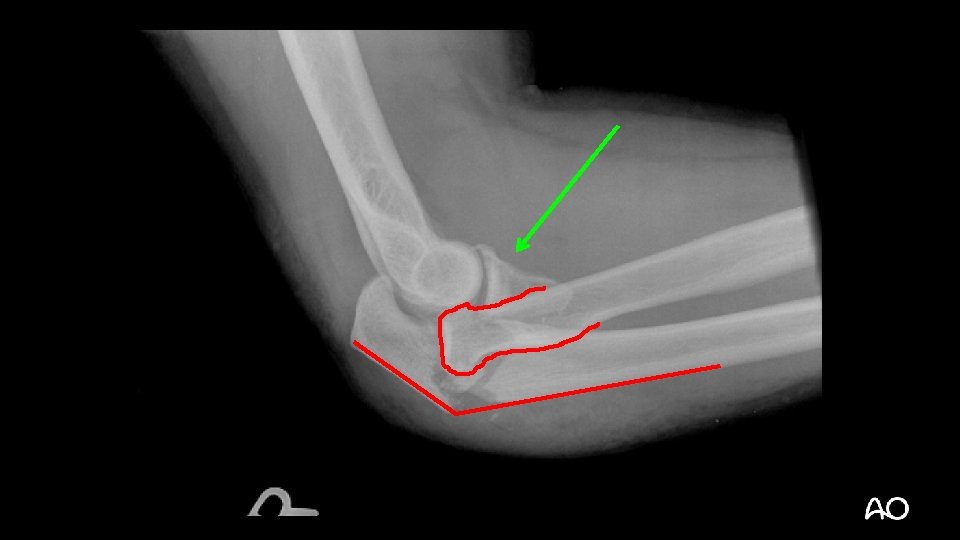

Terrible triad fracture dislocation • Historically poor outcomes • Injury “triad”: • Elbow dislocation (often posterior) • Radial head fracture • Coronoid fracture

Terrible triad • Treatment principles: • Repair coronoid/anterior capsular attachment • Repair or replace radial head • Repair LCL • NEVER CREATE MORE INSTABILITY: • Ignore “small” (fleck) coronoid fractures: • These are NOT “avulsion” fractures by brachialis, as radiologists often like to say on their x-ray reads • Resect radial head without replacing it • MCL does not usually need operative repair

Terrible triad—tactic • Kocher approach to elbow (ECU-anconeus interval) • LCL often avulsed from lateral epicondyle: • “Bare epicondyle” • If resecting the radial head, do it now to improve access to coronoid ECU = extensor carpi ulnaris

Terrible triad—tactic • Repair coronoid or anterior capsule: • Suture tunnels through proximal ulna • Screws • Consider medial approach for plating type III coronoid fractures • Complete repair or replacement of radial head • Repair LCL during closure Regan et al (Orthopaedics. 1992; 15: 845– 848)